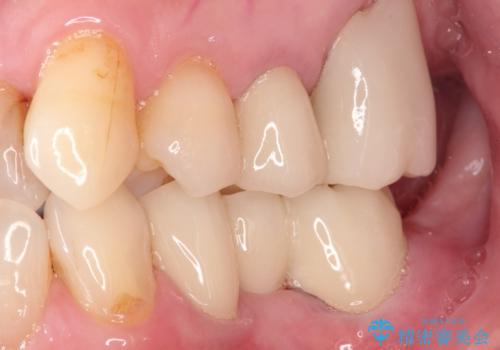

金属のかぶせ物をセラミックへ 根管治療からの再治療

左側の上下の奥歯に適合が悪く、レントゲン上でも根の治療が必要なところがありました。

根管治療からの再治療を行ったことにより、治療期間が多少長くなりましたが、今後再治療の必要性があまりないような、精度の高い治療ができました。